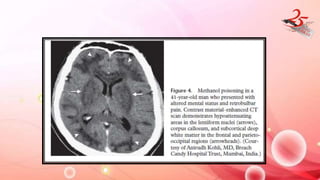

TOXIC POISONING

• CAUSE : MC - CO , methanol and CN

• Impairs mitochondrial enzyme in electron transport chain .

• CLINICAL FEATURES : Acute cognitive impairment /coma , optic

neuritis (methanol)

DIAGNOSIS

• Toxicology and Lab tests , imaging ( assess brain damage)

IMAGING FINDINGS

• CO – GP(MC) : T1 & T2 hyperintense + DWI RD , Delayed

leukoencephalopathy

• CN , Meth : Hemorrhagic necrosis of putamen

• Meth : White matter edema